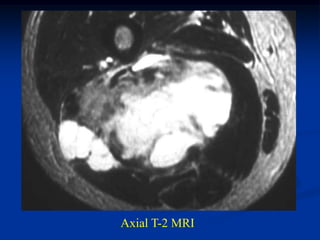

Case #263           Coronal proton density MRI

tumor

72 year female with MFH deltoid muscle

Another proton density coronal cut